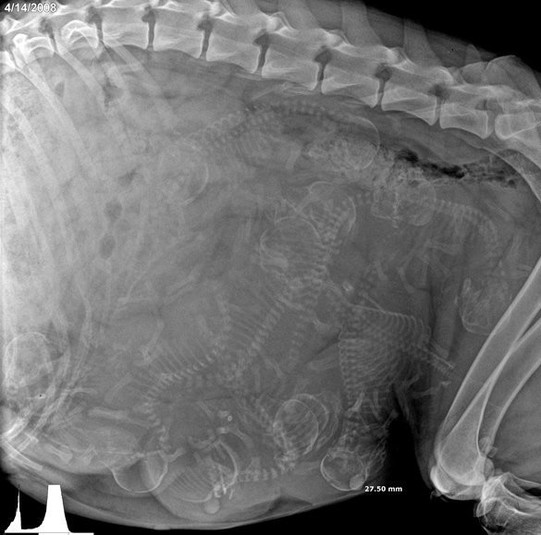

15 удивительных рентгеновских снимков беременных животных

Специалисты, которые по долгу своей работы наблюдают животных, готовых принести потомство, поделились этими удивительными рентгеновскими и ультразвуковыми снимками.